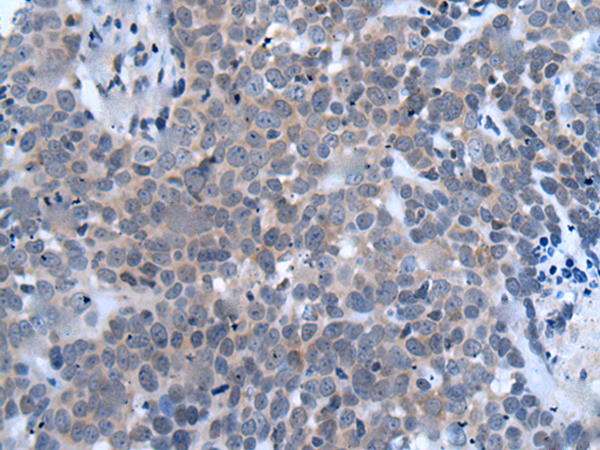

ELISA, IHC |

IHC positive control: |

Human thyroid cancer |

IHC Recommend dilution: |

10-50 |